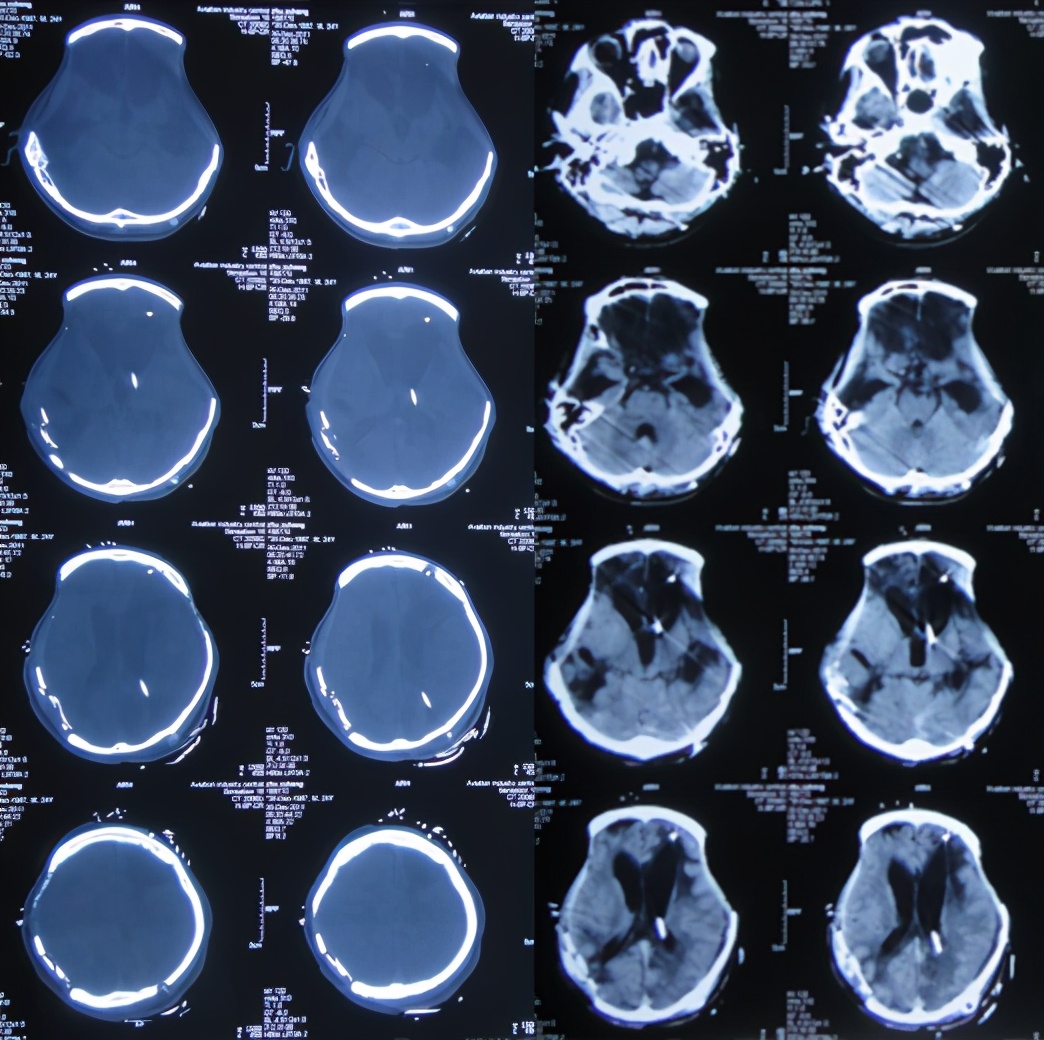

入院治疗21天即2011年11月28日,脑脊液颜色虽清亮,但仍有絮状物( 图-11 );头颅CT示脑积水有改善( 图-12 )。

图-12: 2011年11月28日头颅CT

入院治疗49天即2011年12月26日,例行复查头颅CT( 图-13 )后进行了左侧脑室-腹腔分流术。术后患者肢体较以前灵活,吃饭变正常。

图-13: 2011年12月26日头颅CT

入院治疗53天即2011年12月30日(脑室腹腔分流术后3天),患者肢体较入院时变灵活,吃饭也变正常,头颅CT示脑室缩小,骨窗变塌陷,但发现右侧原手术区有碎骨( 图-15 )。

图-15: 2011年12月30日头颅CT

入院治疗113天即2012年2月28日,查头颅CT示脑室进一步缩小( 图-17 )。

图-17: 2012年2月28日头颅CT

入院治疗127天即2012年3月13日(左侧颅骨修补术后6天),头颅CT示左侧颅骨修补术后,右侧仍有碎骨( 图-18 )。

图-18: 2012年3月13日头颅CT

右颞枕清创探查术后4天即2012年4月29日(入院治疗173天即左侧颅骨修补术后52天),头颅CT示右侧碎骨已清除( 图-19 )。

图-19: 2012年4月29日头颅CT

2012年7月10日(入院治疗248天即左侧颅骨修补术后127天),出院时:右侧颅骨缺损( 图-20 ),意识清楚,能简单言语交流。

图-20: 2012年7月10日头颅CT